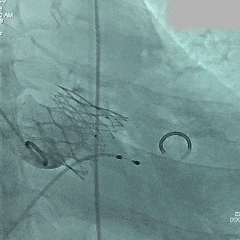

造影评估,瓣膜深度可,无瓣周漏

左头观察,腰征明显,锚定稳定

术后TEE评估

TEE超声评估微量瓣周漏,测压差7mmHg,反流改善明显。